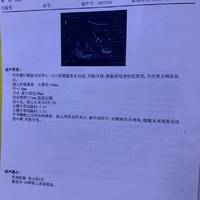

NT检查一次顺利通过

NT检查一次顺利通过,原来在网上看了好多帖子做功课,还买了巧克力什么的,都没用上?。希望孕期检查都能绿灯,顺顺利利生下宝宝。昨天喉咙有一点痒,没放心上,今天喉咙更痒了,痒的时候还必须咳一下才舒服一点,现在好东西会感冒。不晓得是不是心理作用,现在连头都有点晕晕的?...

双胎昨天做了NT检查700有一

双胎昨天做了NT检查700有一个值有点险2.5了,但医生说还是正常在高就不好了,建议我做一个无创筛查两千多,说检查全面一点,还有一个微创一千多的检查的就没那么多,想着只要宝宝健康成长多花点钱也行啦……但是看有的检查费用没有这么高是不是医院不同的问题?...